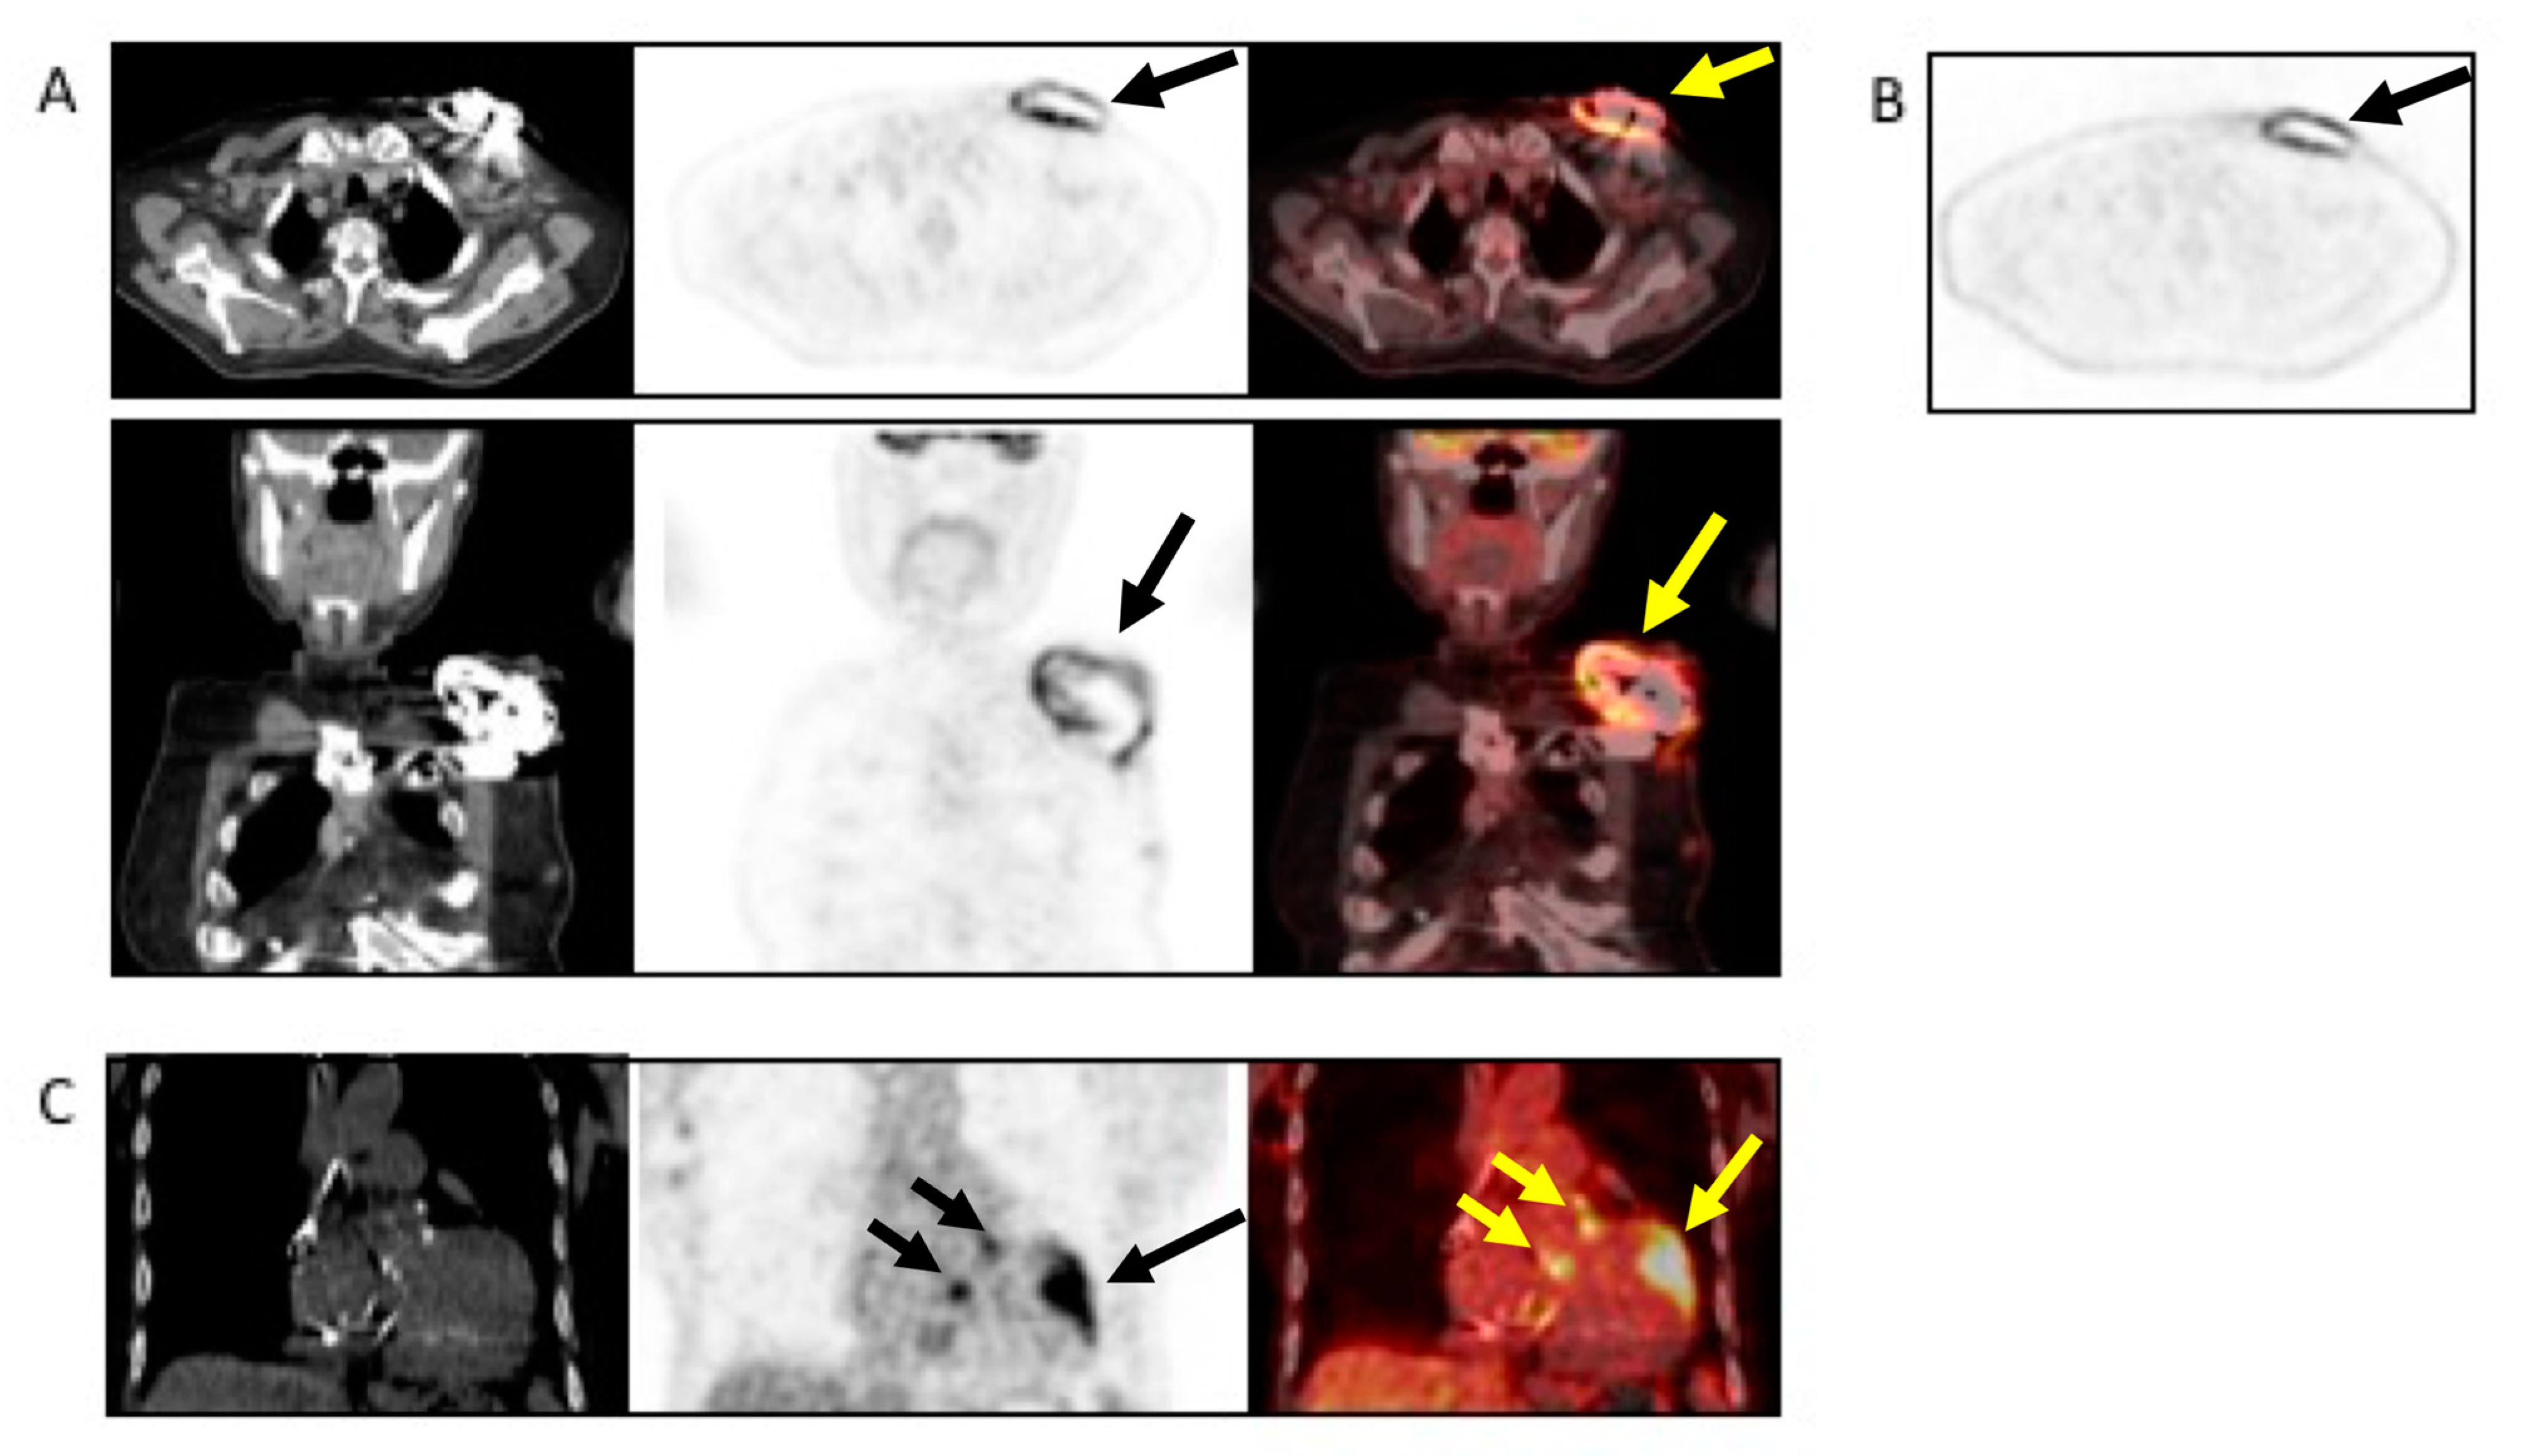

| CIED-IE | Useful to assess intracardiac lead segments. TTE can be integrated by ultrasound evaluation of device pocket, to assessing inflamation or fluid collection. | Limited role in the assessment of unexplorable lead segments. Differential diagnosis of vegetation vs. lead fibrosis/thrombi can be challenging. | Possibility to combine the CT assessment of generator pocket. | Blooming and beam hardening artefacts. Poor sensitivity in detecting vegetations on leads. | Very high sensitivity and specificity for generator/pocket and extracardiac or extravascular lead infection. | Low sensitivity for small vegetations along the leads. | Good sensitivity and specificity for generator/pocket and extracardiac or extravascular lead infection. | Limited diagnostic sensitivity for intracardiac and intravascular lead infection. | Image quality severely hampered by susceptibility artifacts from lead and device. Limited to patients with MRI conditional devices and with numerous precautions. | |

- Chest CT has a specific role in searching for pulmonary embolism, infarct or abscess. The (18F)FDG PET/CT and WBC SPECT/CT have a central role in detecting pocket infection, lead infection, and pulmonary embolism.